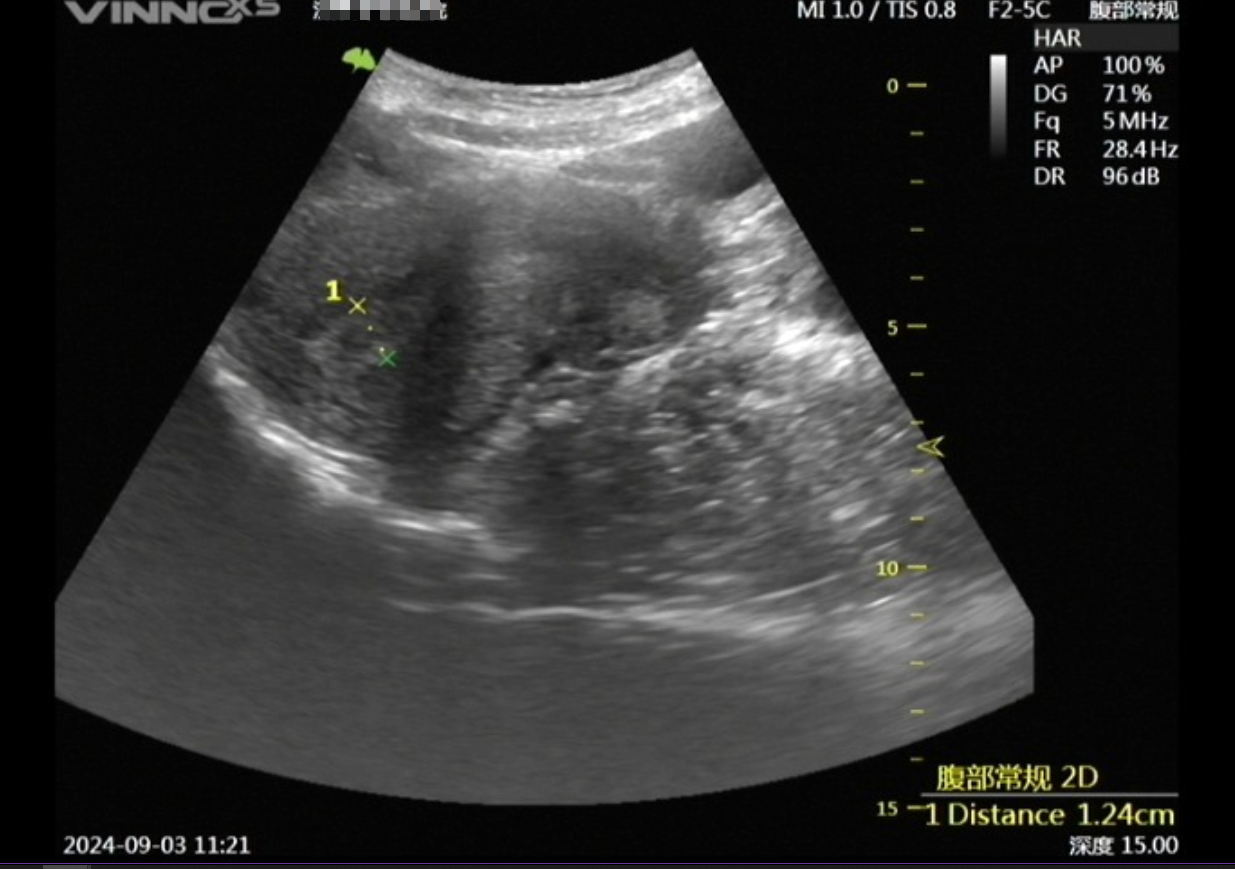

嘉利达医疗US检查影像数据集

医疗US检查影像数据集,包含匿名化的患者基础信息(性别、年龄区间、检查部位和检查报告)内容,可应用在患者预后评估、疾病风险预测、医疗资源优化、医学研究等方面。如:1.患者预后评估:···

广州数据交易所